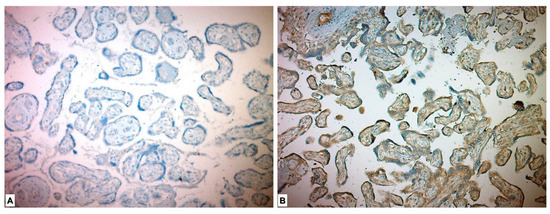

3.3. Immunohistochemical Results

| FGF21 | <0.001 * | ||

| High Expression | 55 (98.2) | 0 | |

| Low Expression | 1 (1.8) | 43 (100) | |